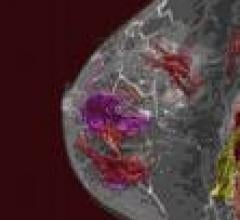

Magnetic resonance imaging (MRI) can be used for breast imaging as an alternative to mammography.

As breast magnetic resonance imaging (MRI) becomes a more widely accepted modality for breast cancer screening of women ...

August 24, 2009 - Breast MRI allows physicians to evaluate suspicious lesions using a variety of variables and computer ...

April 23, 2009 - 3T MRI can detect a significant number of lesions not found on mammography and sonography, according to ...